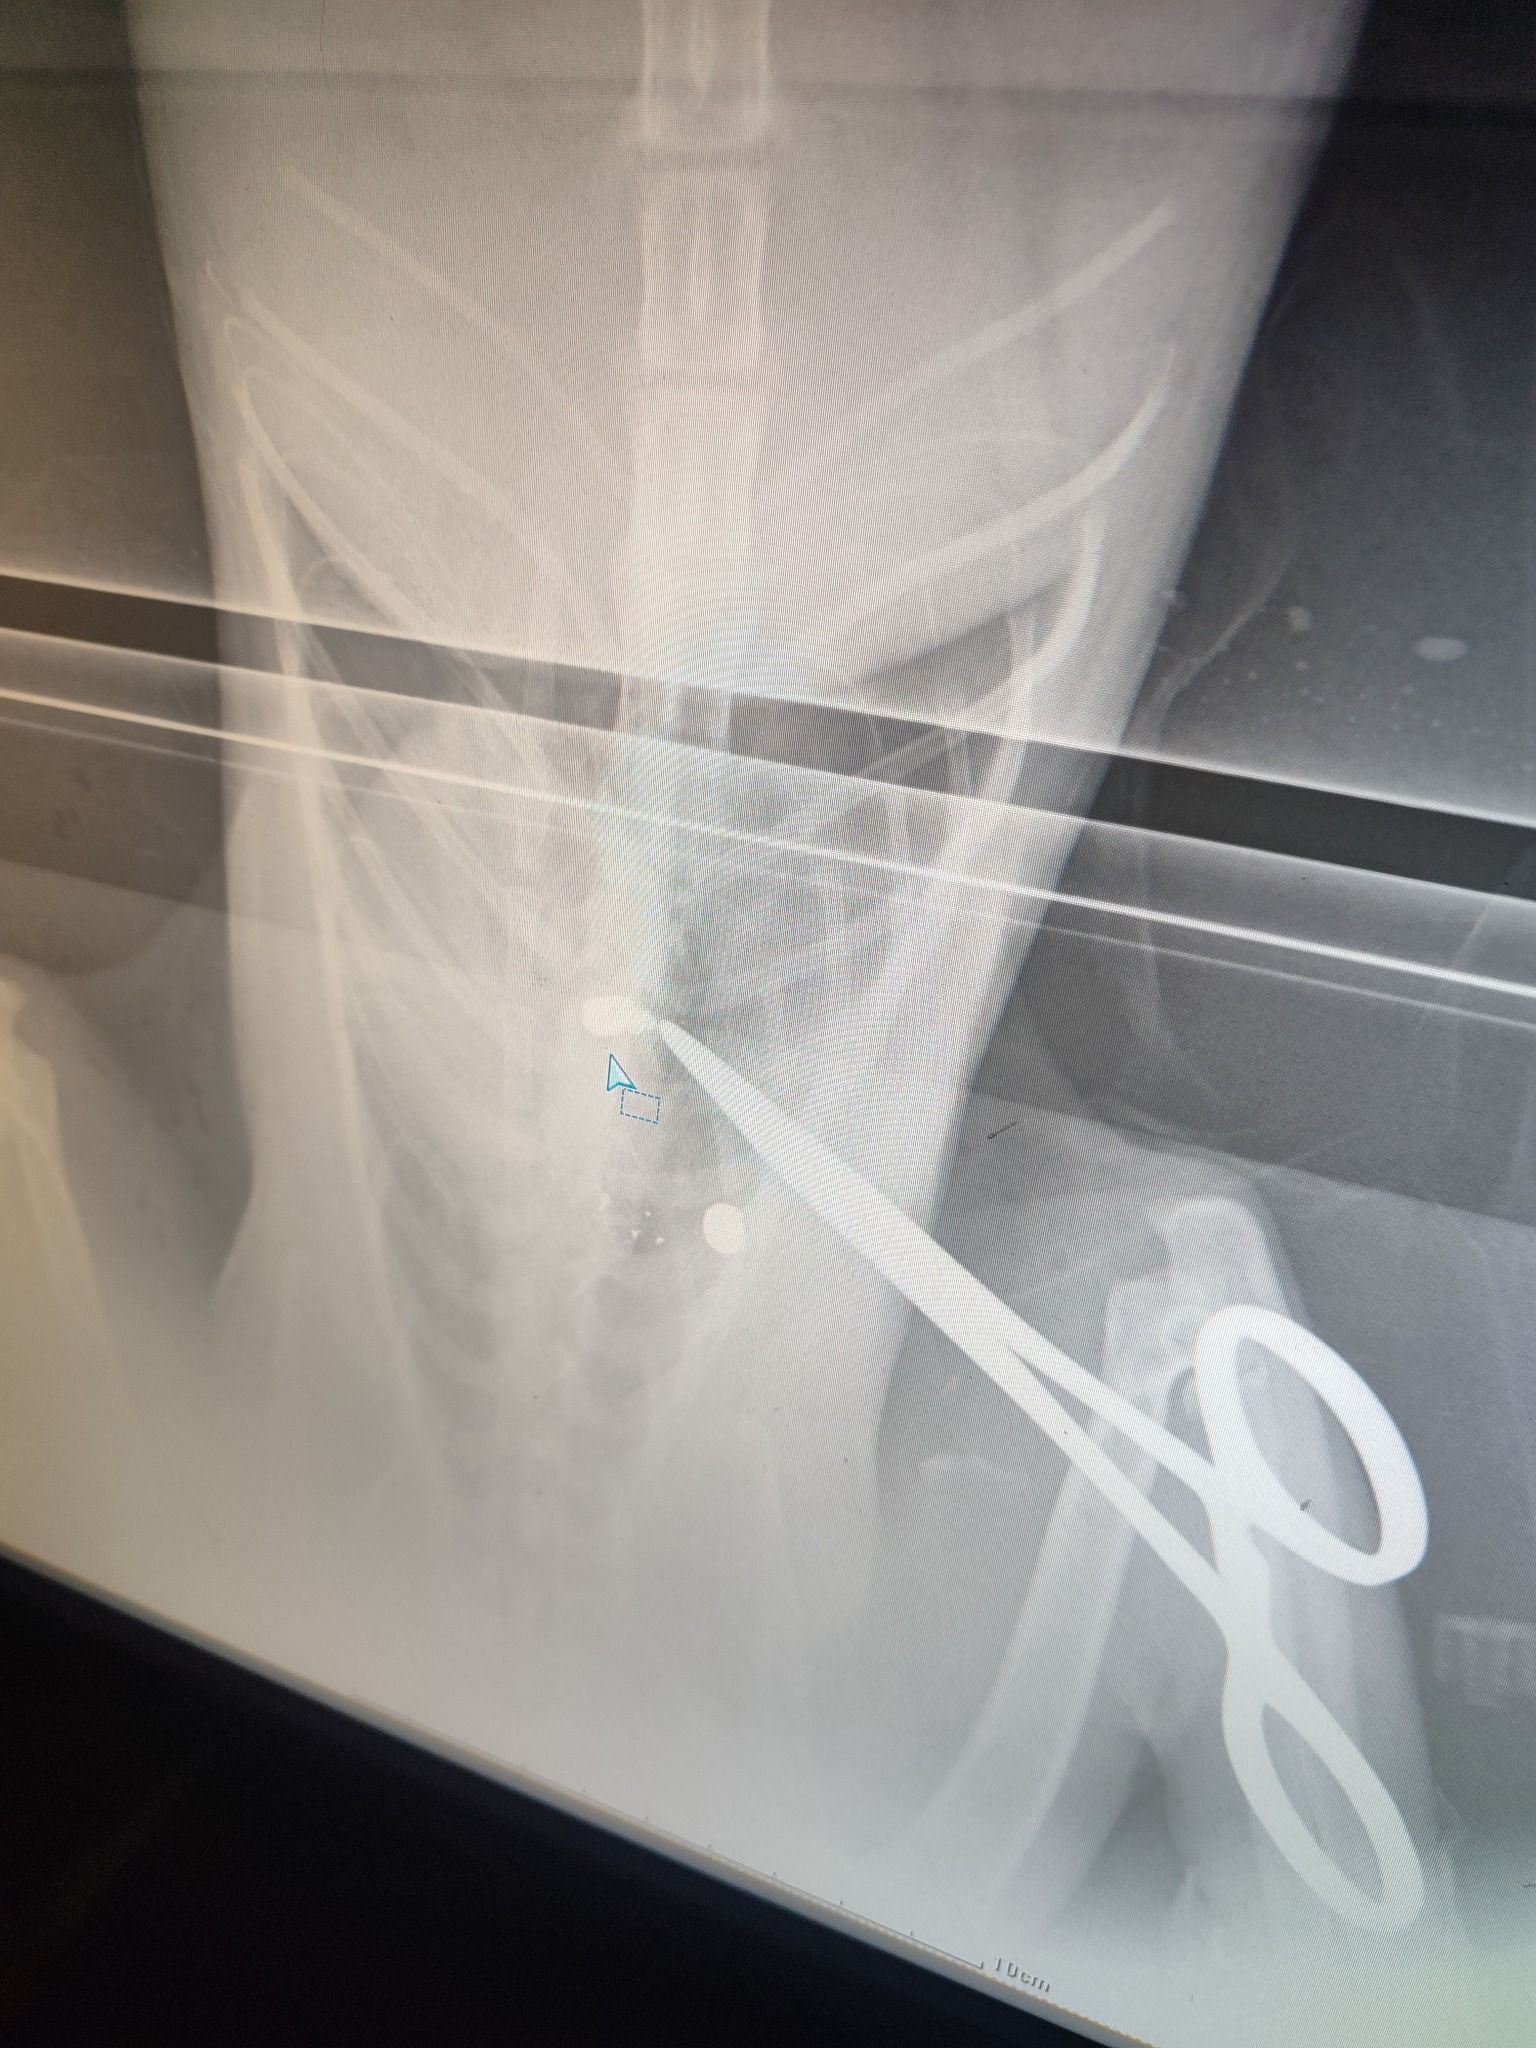

Το ζώο, όπως έδειξαν οι ακτινογραφίες, είχε πυροβοληθεί με αεροβόλο δύο φορές. Το ένα σφαιρίδιο είχε καρφωθεί στην σπονδυλική του στήλη και αν δεν είχε πάει επί τόπου ο εθελοντής διασώστης Κώστας Μαμασούλας, ώστε και να το πιάσει και να το μεταφέρει σε κτηνιατρική κλινική, η γάτα θα ήταν ήδη νεκρή και θα είχε μαρτυρικό θάνατο…

Οι πιθανότητες να περπατήσει είναι λιγες, ωστόσο αποφασίστηκε να κάνει το χειρουργείο και να του δώσουμε έστω αυτή την μικρή πιθανότητα ώστε να βγει η σφαίρα που είχε σφηνώσει στην σπονδυλική στήλη και να αποσυμπιεστεί. Τώρα το μόνο που μας μένει είναι να περιμένουμε, καθώς είναι πολύ δύσκολο ζώο και καθόλου συνεργάσιμο.».